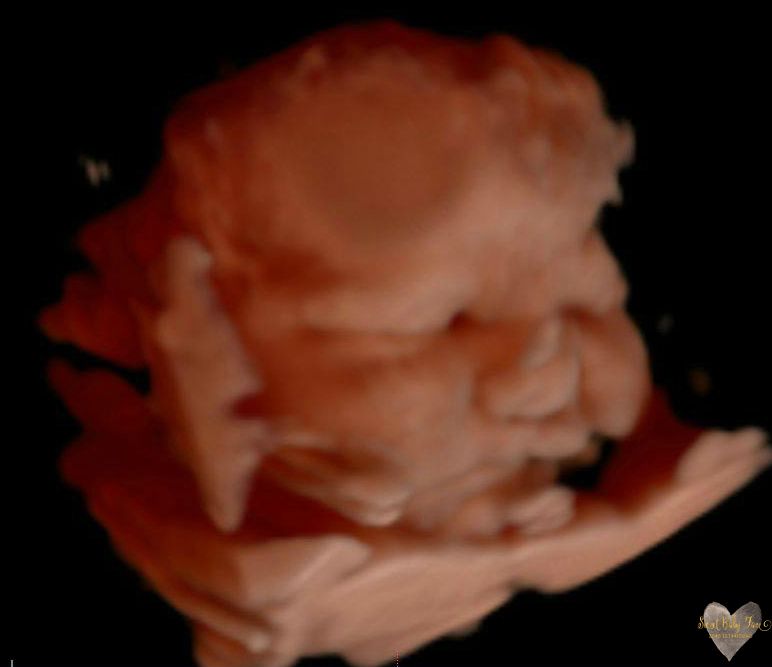

3D/4D/5D Ultrasound Gallery

Take a peek at our Photo Gallery. All of our 2D, 3D, 4D, HD elective ultrasound images are truly ours. They come directly off our machine from our highly trained staff. We can start getting great 3D/4D images as early as 10 weeks!